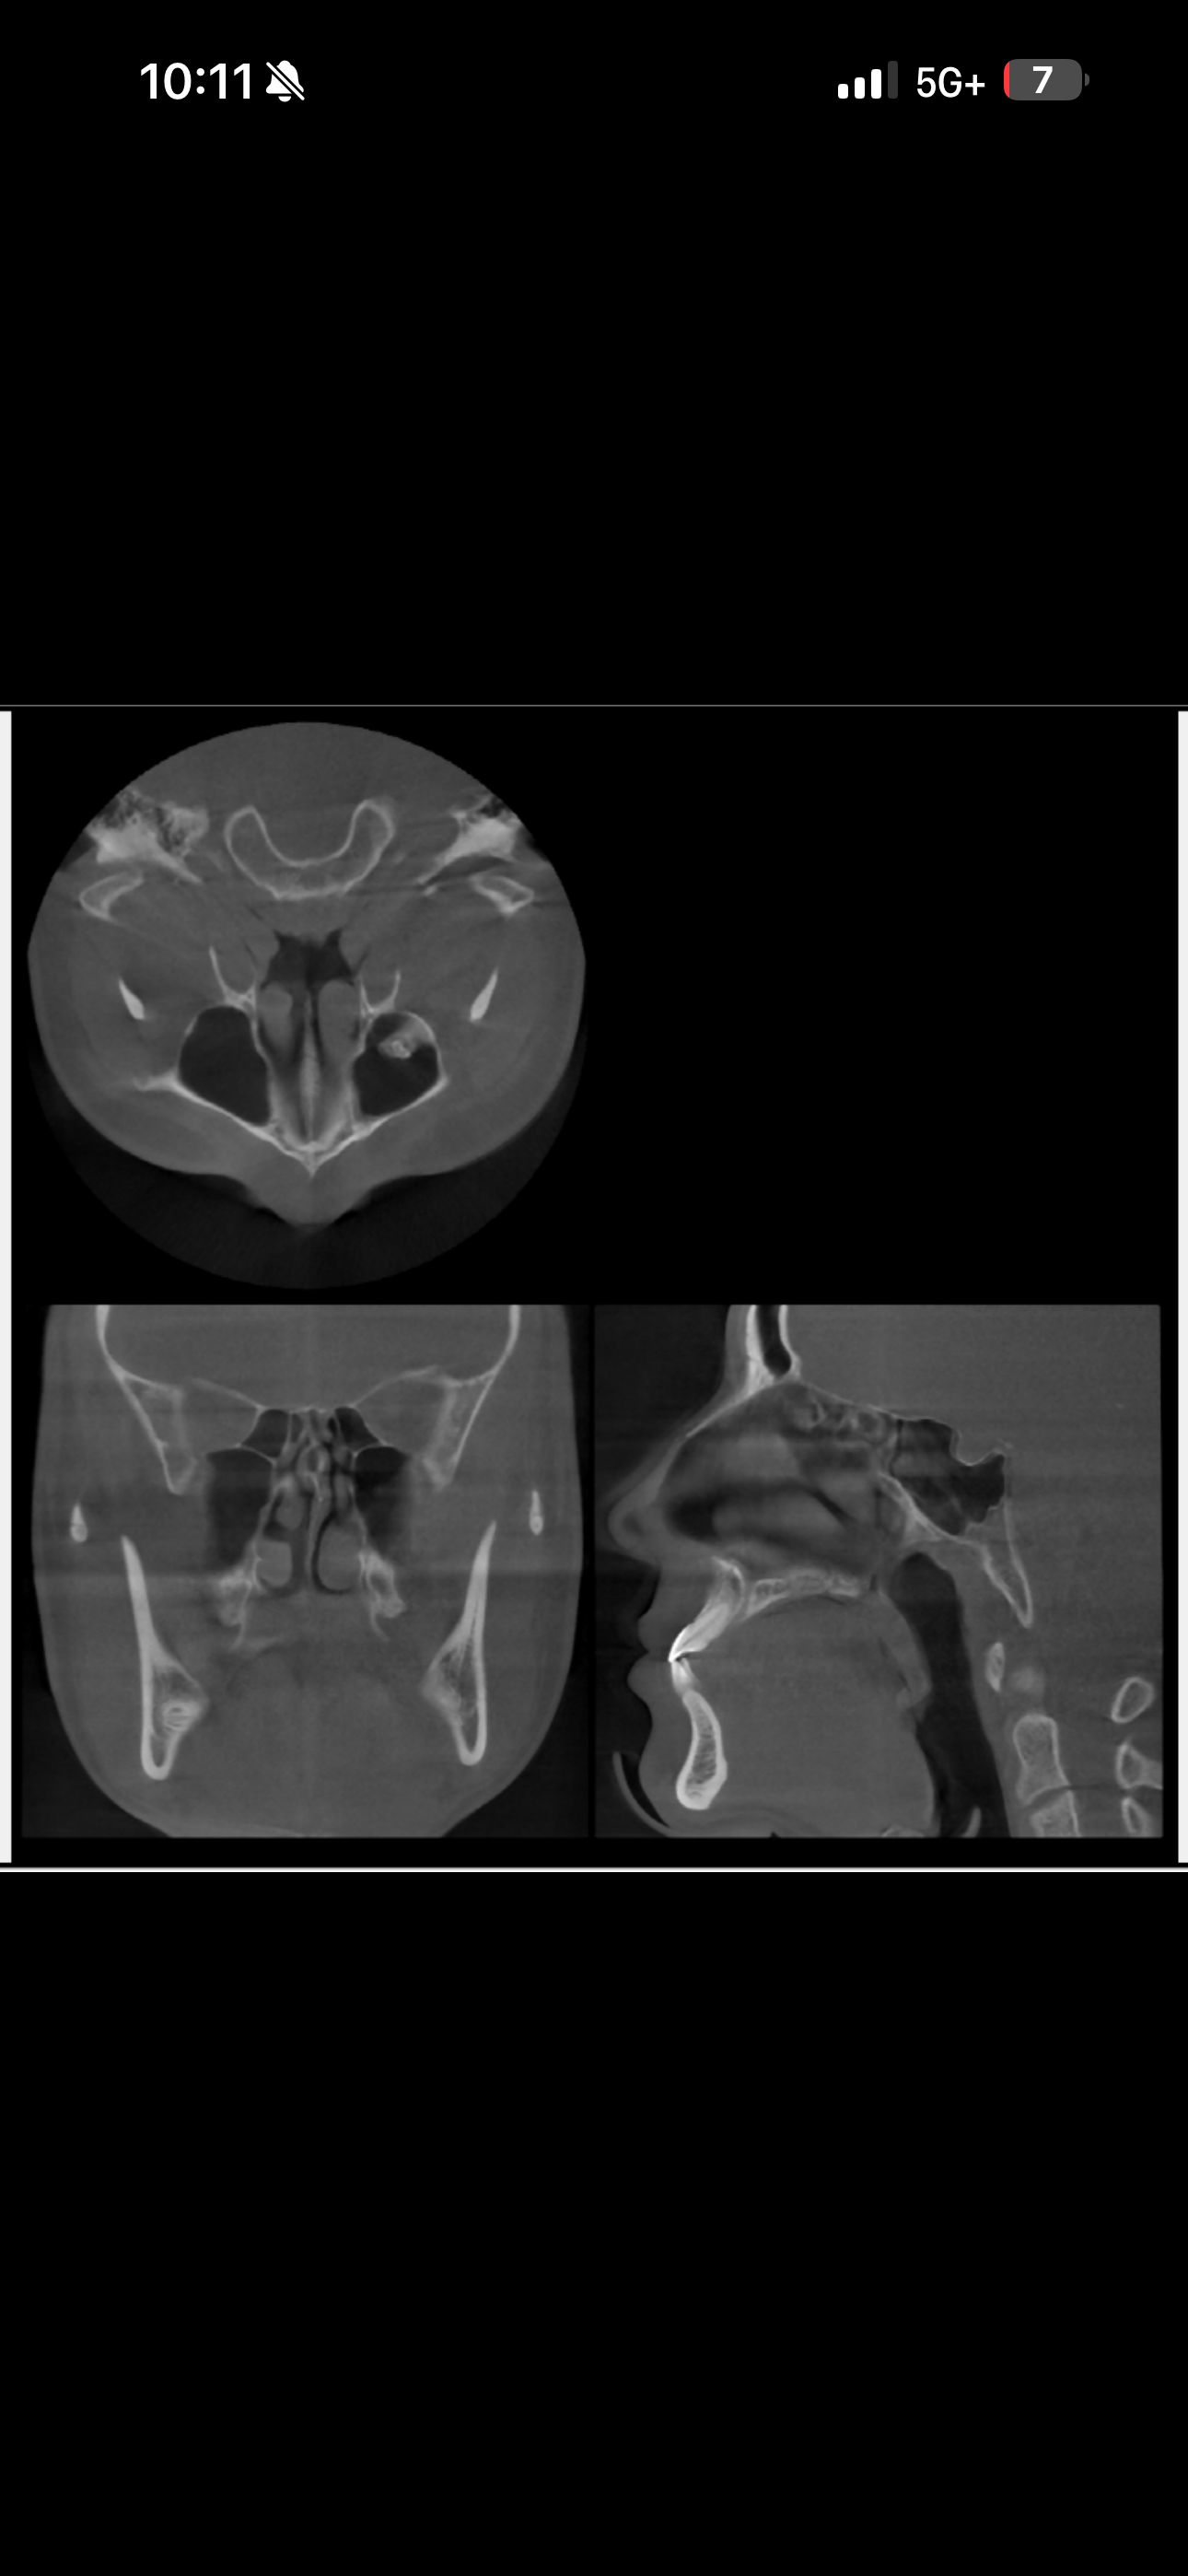

from cbt scan

Good job posting it on a grey filled subsection , im sure people are gonna understandfrom cbt scan View attachment 4450191